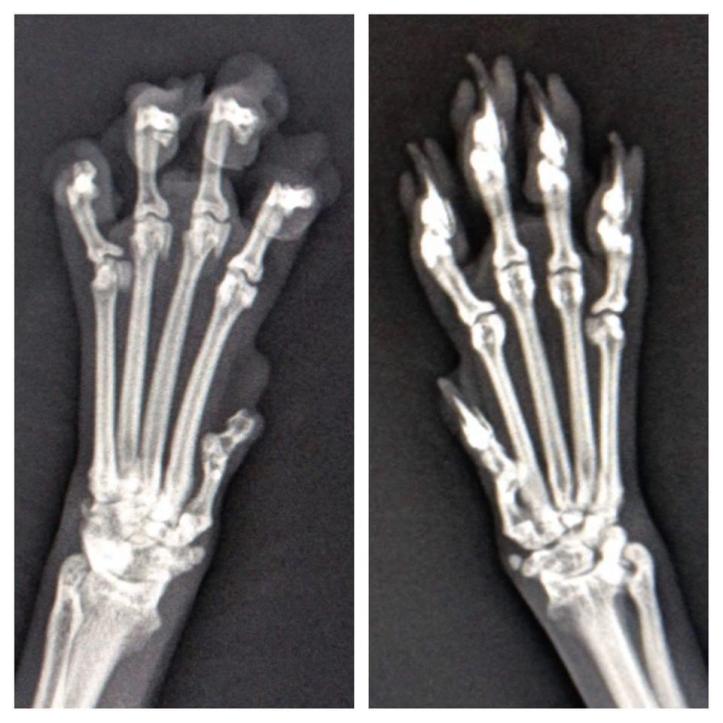

Are you considering declawing your cat? Since a cat’s claws grow from their bones, declawing is an amputation. Veterinarians use Resco nail trimmers that look very similar to the guillotine nail clippers we use to trim their nails to cut off the tip of their paws. This procedure is similar to a physician using a cigar cutter to remove the tips of our fingers down to the third knuckle. Veterinarians also use lasers which may be even more painful since they burn the skin in addition to cutting the bone.

The procedure takes 3-4 minutes per paw and not only amputates but severs two important tendons, the deep digital flexor and extensor tendon which control movement of the forearm, wrist and claws.